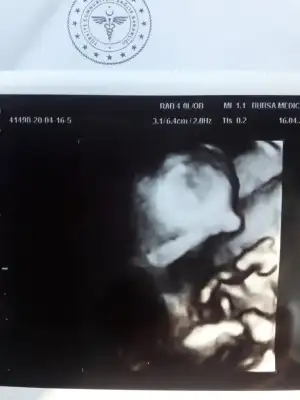

15+3

Saglıkla gelsin ogluşunTahminin doğru çıktı canım bebegim erkekmis bugün öğrendik oyluyorum hemenIkra meyra

29 nisanda ayrıntılı ultrasonumuz var. malum gundemden dolayi pek hastaneye gidemedigimiz için daha kesin öğrenemedikÖgrendinizmi kızmı![]()